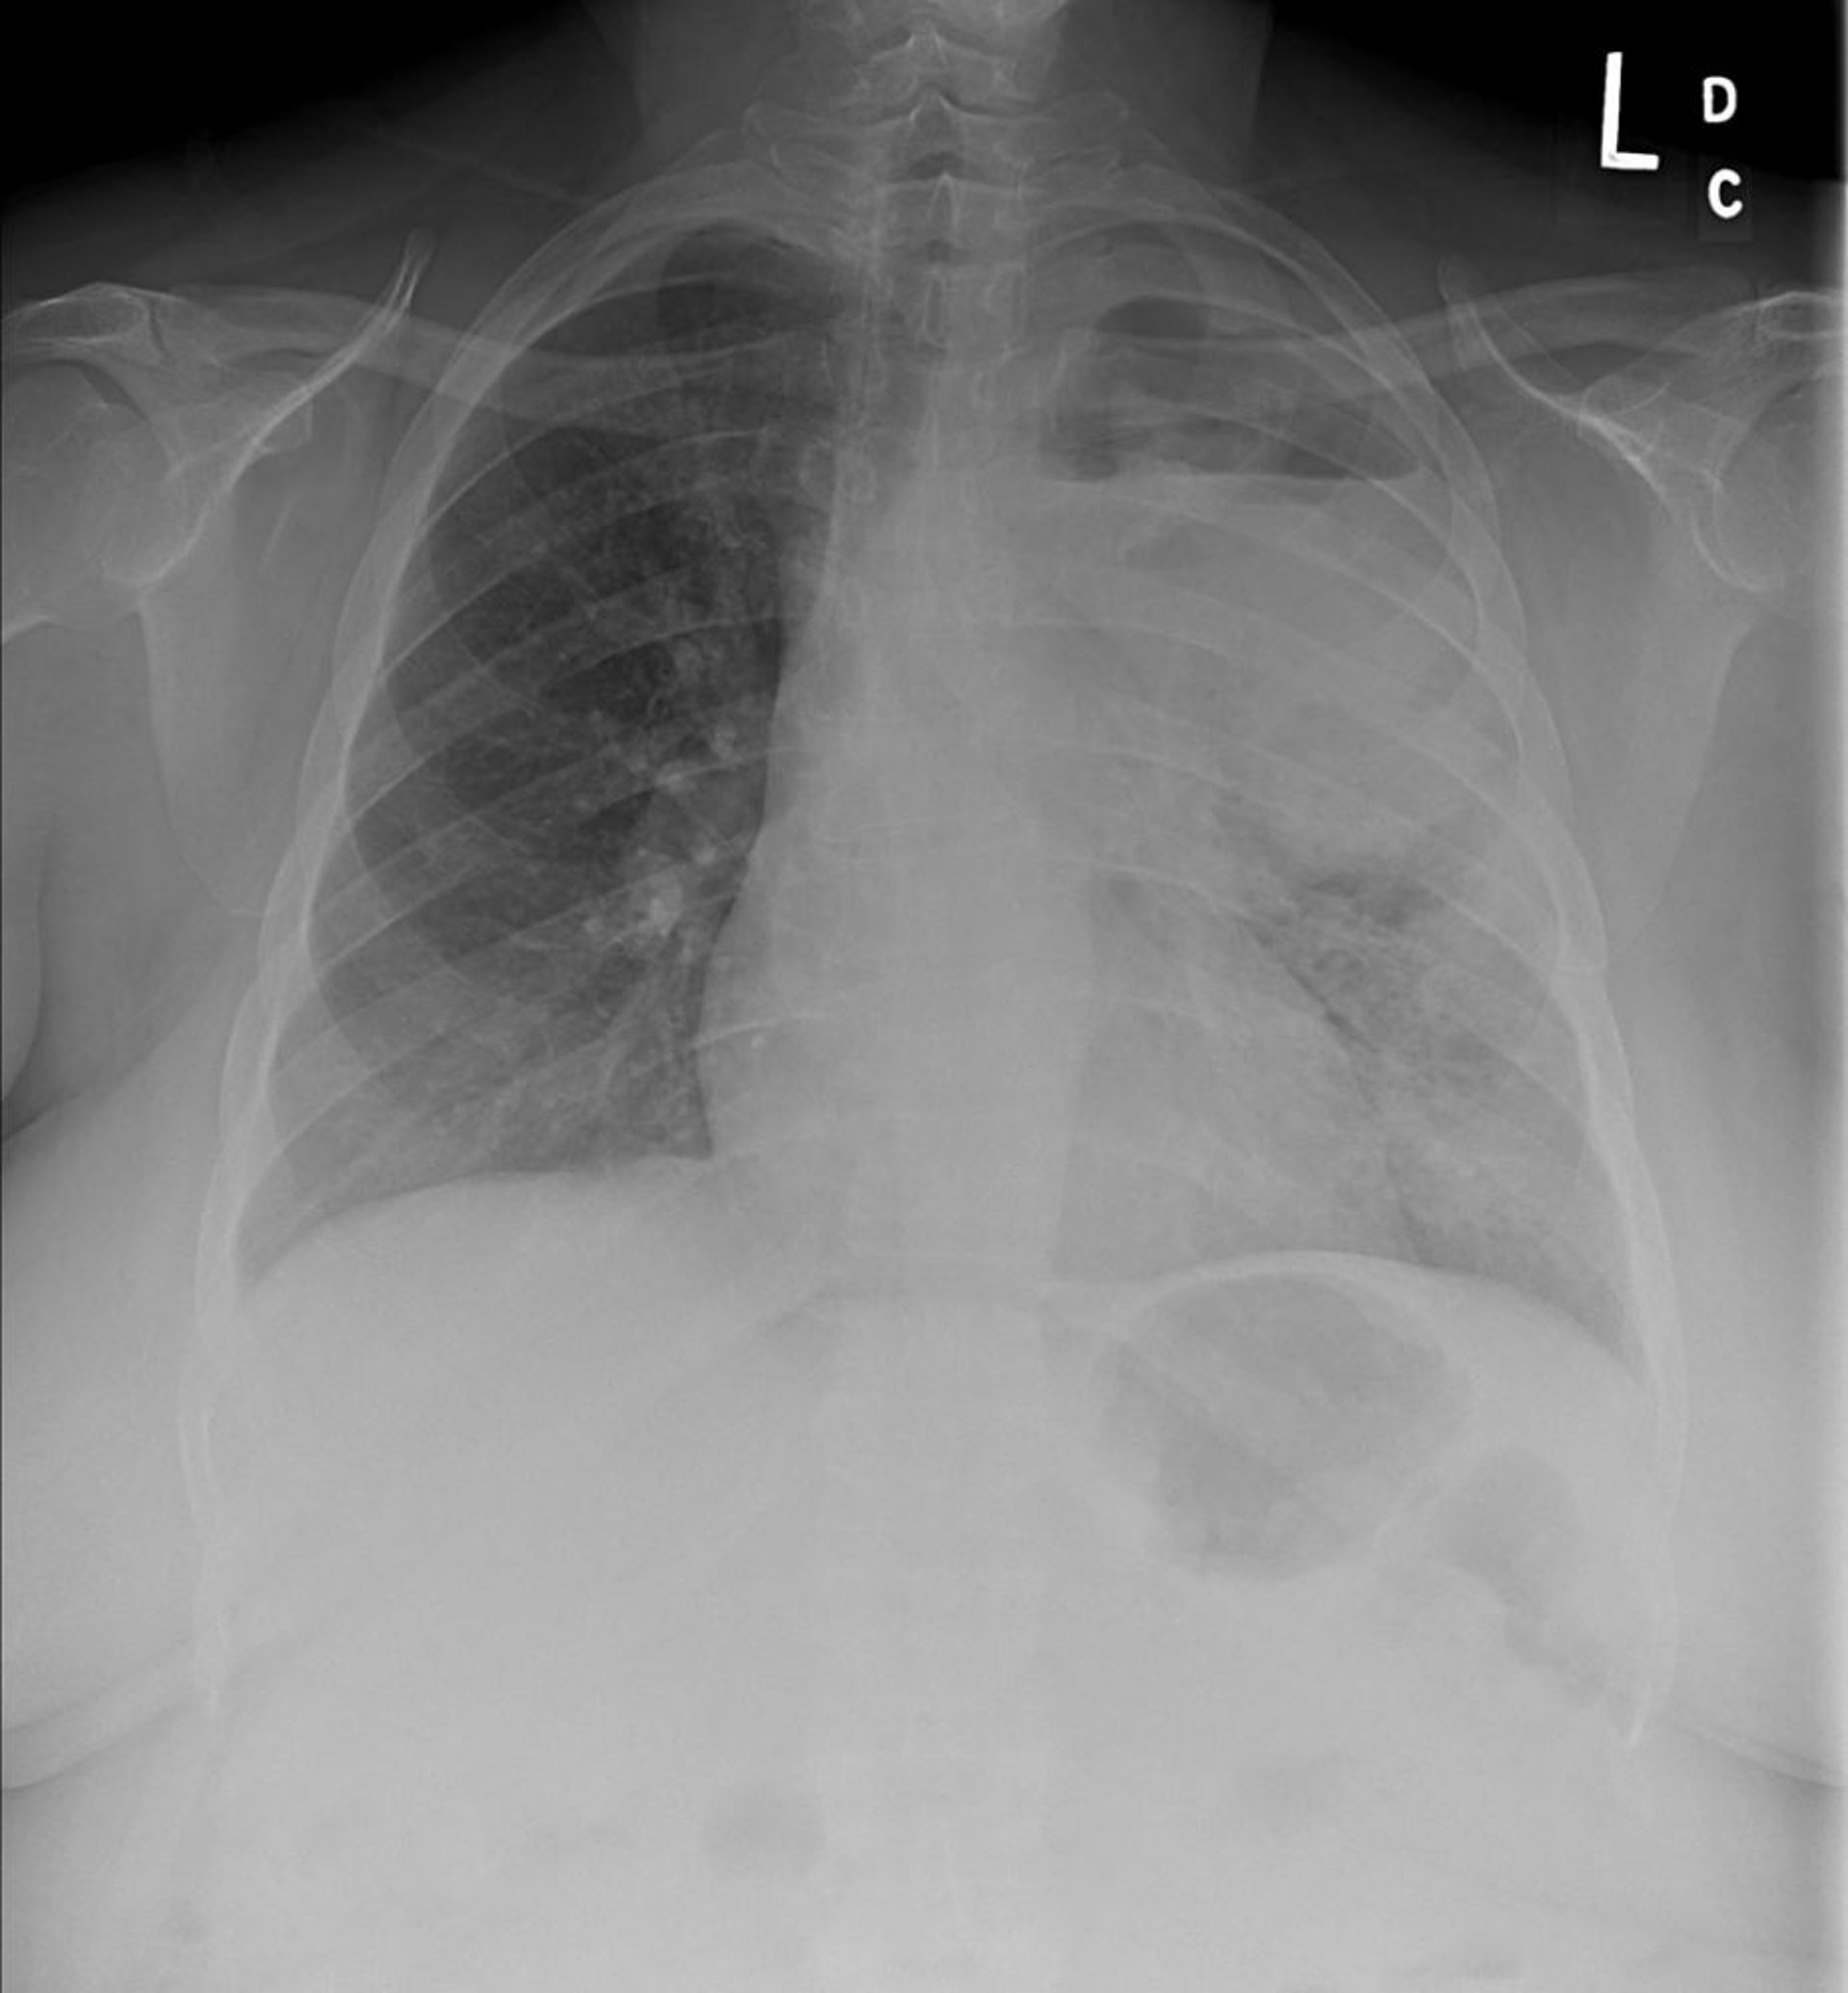

La rx thorax est souvent l'imagerie initiale. Elle peut montrer des anomalies clairement définies, telles qu'une masse unique ou des masses multifocales ou un nodule pulmonaire isolé Nodule pulmonaire solitaire Le nodule pulmonaire solitaire est défini comme une lésion en apprendre davantage ou d'autres anomalies, telles qu'un élargissement du hile pulmonaire, un gros médiastin, un rétrécissement trachéobronchique, des atélectasies, un infiltrat parenchymateux non résolutif, une lésion cavitaire, un épaississement ou un épanchement pleural inexpliqué. Ces anomalies sont évocatrices, mais non spécifiques du cancer du poumon et nécessitent de poursuivre les investigations par une TDM, ou une association PET–TDM et par confirmation cytopathologique.